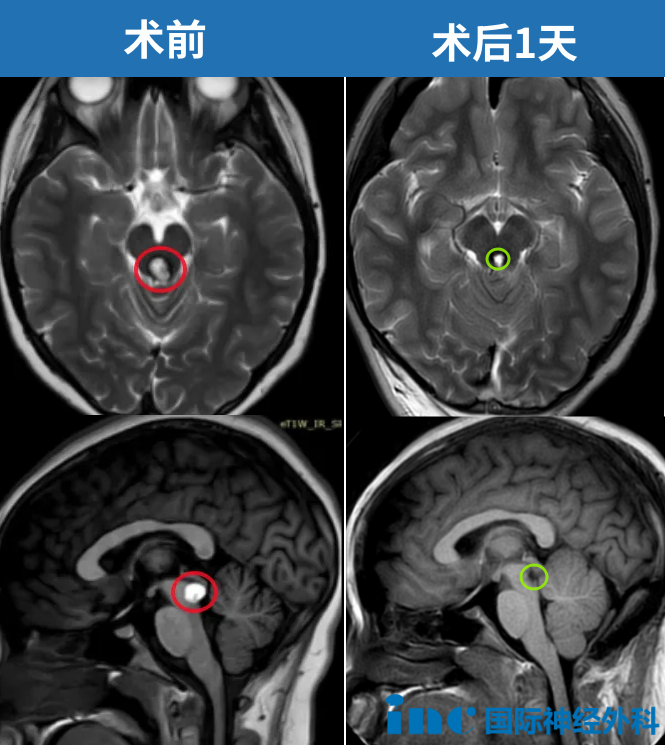

2024年8月5日,湘湘的手术在苏州大学附属儿童医院顺利开展,术后核磁显示,病灶全部切除。

术后3个月随访,MRI复查的影像显示出血性海绵状血管瘤已完全切除,未见任何不良后果。